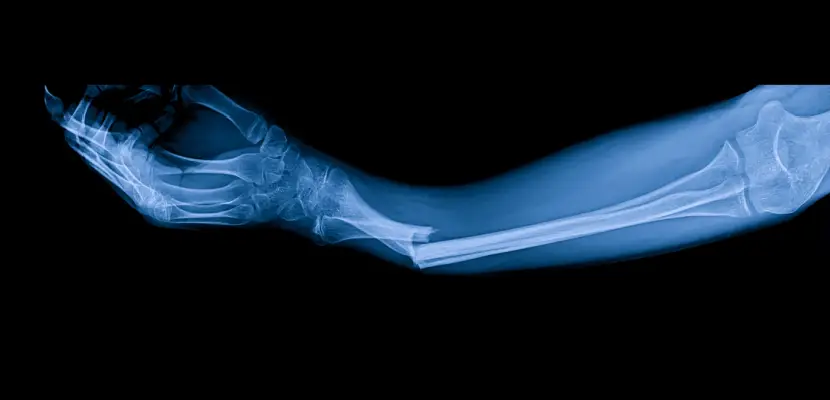

Understanding The Different Types Of Fractures

Fractures vary widely in severity and complexity. Some may heal with immobilization, while others require surgical repair and long-term therapy. Common fracture types include:

- Simple Fractures: Clean breaks where the bone remains aligned.

- Compound Fractures: The bone pierces through the skin, raising infection risks and often requiring surgery.

- Comminuted Fractures: Bones shatter into multiple pieces, usually needing plates, rods, or screws for stabilization.

- Displaced Fractures: The bone ends are misaligned, demanding corrective procedures.

- Stress Fractures: Small cracks often caused by repetitive strain, sometimes mistaken for minor injuries but capable of significant disruption.

The type of fracture impacts treatment, costs, and recovery time. Our attorneys work with orthopedic specialists to ensure your legal claim accounts for the true extent of your injury.